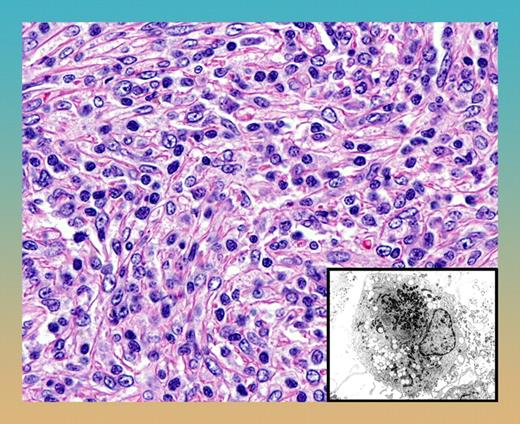

Follicular dendritic-cell sarcoma with syncytial proliferation of spindle cells. Note the characteristic sprinkling of lymphocytes within the tumor. The inset shows the ultrastructural appearance of dendritic cells with villous cell processes and prominent lysosomal granules.